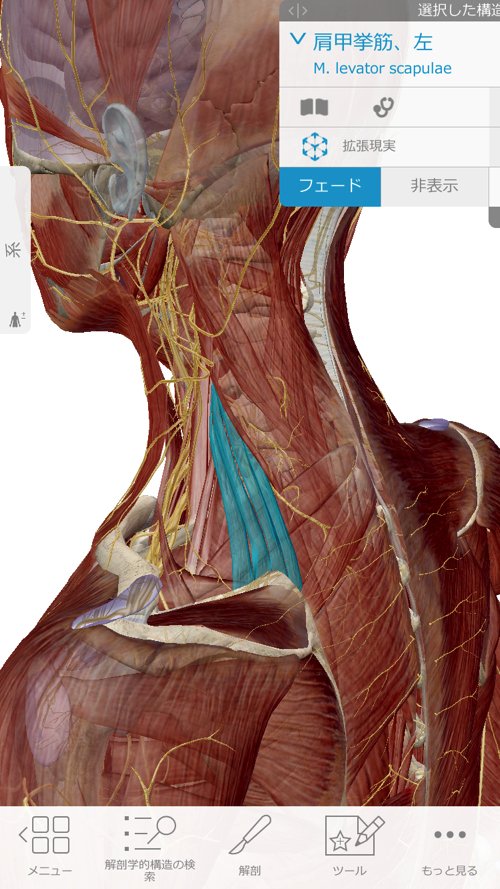

肘に硬直やヨジレがあると、こんな感じで繋がっている肩や肩甲骨が

下に引っ張られてズレたり、動かせなくなったりします。